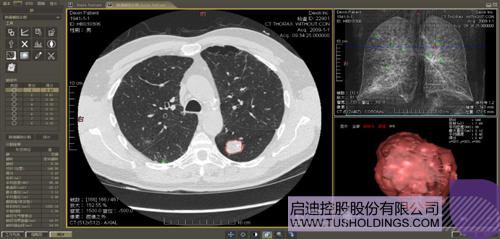

數(shù)字肺產(chǎn)品肺癌計算機輔助診斷

醫(yī)療影像智能分析是指運用人工智能技術、計算機視覺技術以及計算幾何技術對醫(yī)療影像進行自動分析,幫助醫(yī)生定位病癥、分析、跟蹤病情,并通過量化數(shù)據(jù)輔助醫(yī)生做出診斷,目前其旗艦產(chǎn)品“數(shù)字肺”已經(jīng)覆蓋多種肺部疾病的早期檢測、診斷、跟蹤、術前規(guī)劃等完整的醫(yī)療流程。在臨床實踐中,超過80%的醫(yī)療數(shù)據(jù)來自醫(yī)療影像,這些影像數(shù)據(jù)通常需要專業(yè)醫(yī)生進行解讀,工作的重復性高、效率偏低。如果能夠運用智能影像分析技術,同時結合臨床表現(xiàn)以及既往病例進行全面分析,那么就可以大幅度提升影像診斷效率和準確性,讓專業(yè)醫(yī)生的寶貴時間集中在復雜病情的診斷和治療等環(huán)節(jié)。

肺動脈栓塞輔助診斷